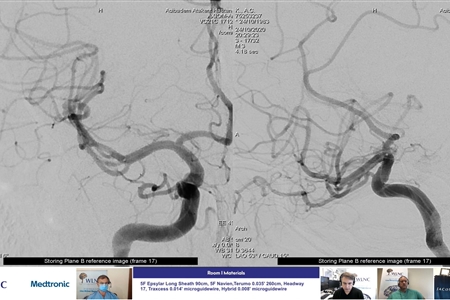

WLNC LIVE & WARM-UP CASES

WLNC 2020 - SECOND DAY

WLNC 2020